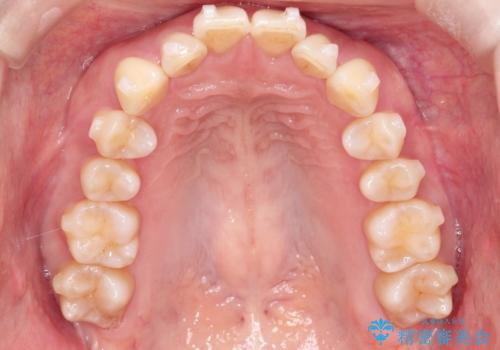

- 前歯が出ていることを主訴に来院されました。

インビザラインにて臼歯部の遠心移動及びIPRを行なっています。

叢生量が多いケースでしたが、綺麗な歯並びとなり患者様にも満足していただきました。